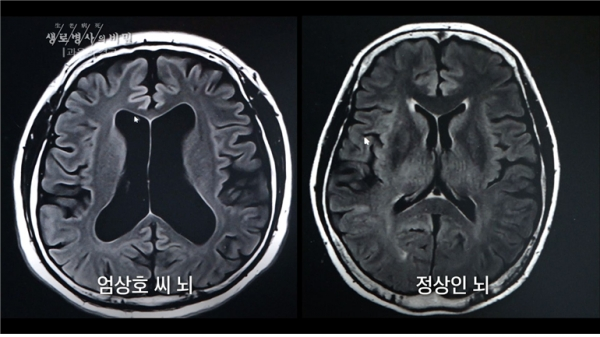

술을 마시는 동안 인간의 뇌는 고통받는다. 잦은 음주와 과음은 블랙아웃 증상을 일으키고, 술 없이 잠에 들지 못하게 만들기도 한다. 기억력에 영향을 주는 알코올성 치매로 번지기도 한다.

이날 ‘생로병사의 비밀’에는 알코올성 치매 전 단계와 ‘알코올 사용 장애’(알코올 의존증, 알코올 중독증) 판정을 받은 두 사람의 사례를 통해 잦은 음주와 과음이 우리 뇌에 미치는 영향과 치료법을 알아본다.

알코올성 치매가 중증으로 진행되면 치료가 어렵다고 한다. 하지만 알코올 사용 장애와 알코올성 치매 전 단계까지는 술을 끊으면 회복할 가능성이 있다고 한다. 이 때문에 알코올로 기억력이 떨어진다고 느끼면 검사와 치료가 필요하다고 예고했다.